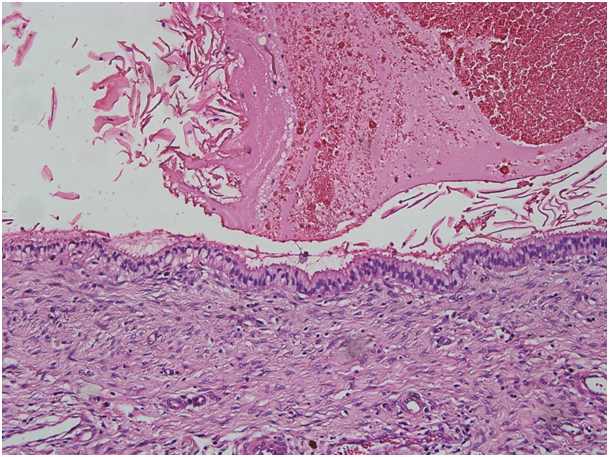

The vaginal cytologic examination was normal. We decided to excise persisting large sized cyst to exclude malignancy. We performed a total excision of the cyst under general anaesthesia. The diagnosis of nabothian cysts was done with the pathologic evaluation that showed retention cyst wall lined by ciliated columnar epithelium without atypia [Table/Fig-2] (H&E, 200X).

Nabothian cyst, the ciliated columnar epithelium without atypia (H&E, 200X)

Histopathologically, nabothian cysts are lined by single layer of columnar epithelium or flattened epithelium without cellular mitosis or atypia as in our case. Huge nabothian cysts need a pathologic diagnosis to exclude other tumours of cervix and adenoma malignum that contains well-differentiated glandular cells with atypia and mitosis. Adenoma malignum (AM) is also called minimal deviation adenocarcinoma and is quite a rare phenomenon. It mimics an appearance of deep and larger sized nabothian cysts. Papanicoula smear screening and cervical punch biopsies may not detect the AM lesion. Similarly, pap smear of our case was normal. Histopathologically, the lesion shows a benign histological appearance and it contains well-differentiated mucinous glands, deeply invading the cervical stroma. Despite benign histopathologic findings, the clinical behaviour is aggressive. Thus, it is a diagnostic challenge and accurate diagnosis is important and depends on high suspicion of gynaecologist [6–8].